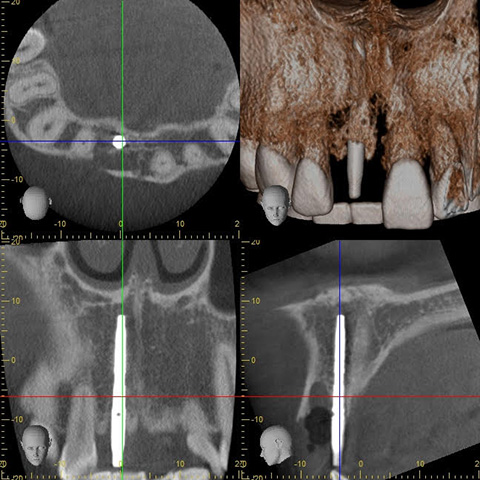

CT写真でもインプラントの埋め込まれた位置に問題がないかをチェックします。

CT写真でも、術前のシミュレーションと差が生じていないかを確認します。

再度CT写真を撮影をして、インプラントポジションを細かくチェックします。